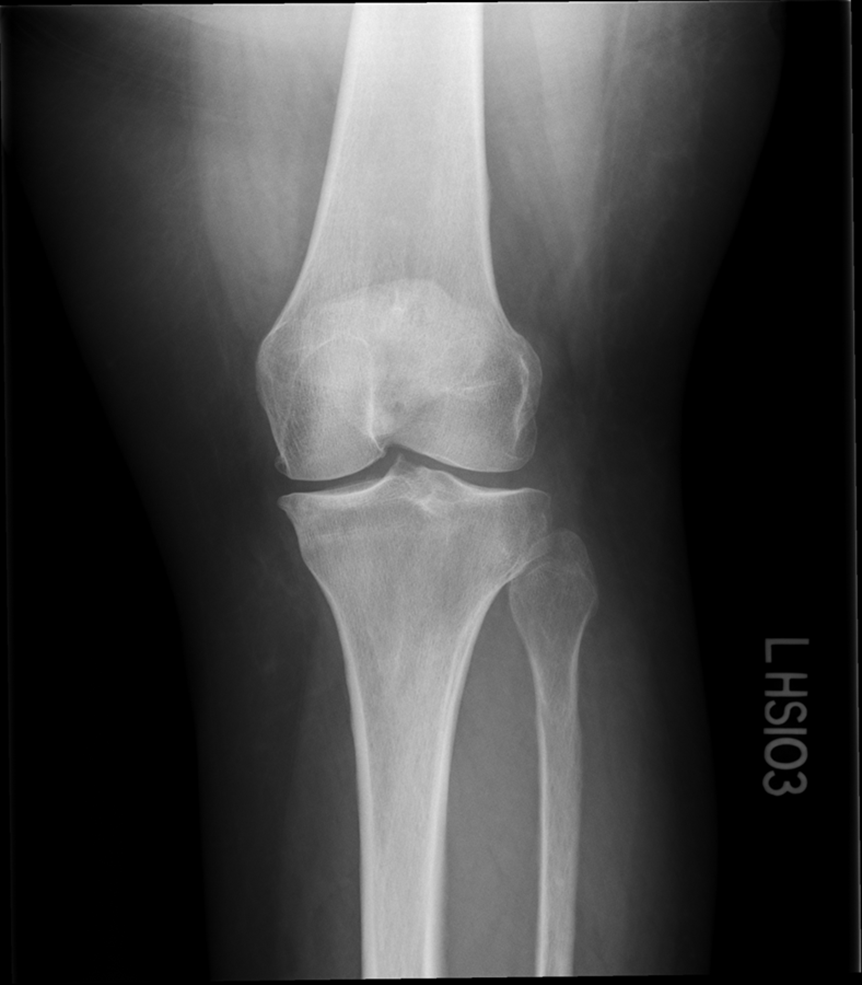

Non Trauma PA Erect (RH)

(patient age 40 and older)

•Evidence of proper collimation and the presence of a side marker placed clear of the anatomy of interest

•Both knees without rotation (RH only does the side of interest)

•Knee joint spaces centered to the exposure area (RH only does the side of interest)

Bony trabecular detail and surrounding soft tissue

joint space is narrowed off, condyles look symmetric

platues look equal

slight superimposition of tibia/fibula

GOOD IMAGE repeat for exposure index